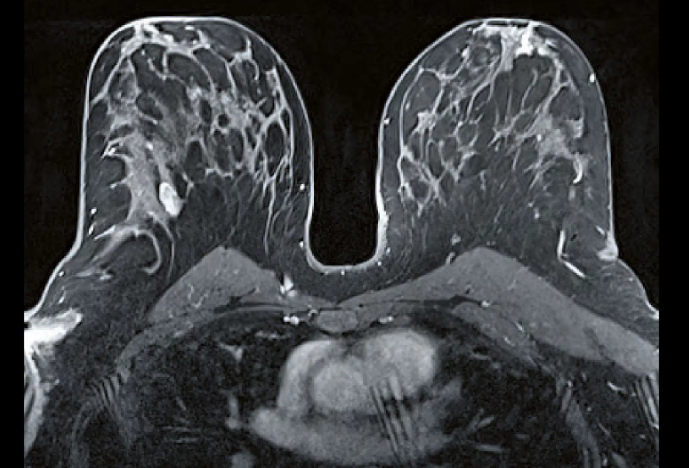

Mamografia, ultrassom e ressonância — quando cada exame é indicado e qual a relação custo-benefício.